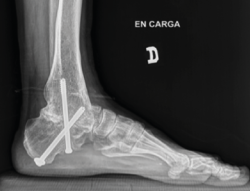

Figura 5. Control por radioscopia del aloinjerto.

- Tallado del injerto de manera intraoperatoria (Figuras 4 y 5).